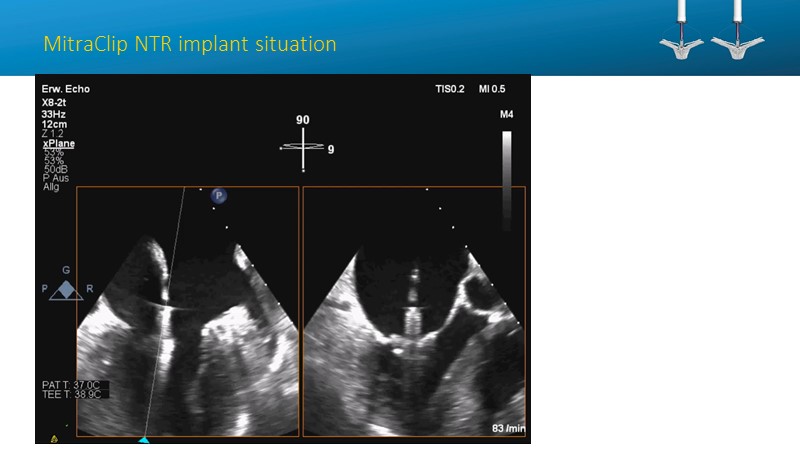

- To learn how will product innovation (Mitraclip NTR / XTR) drive improvement in procedural and clinical outcomes (EXPAND)